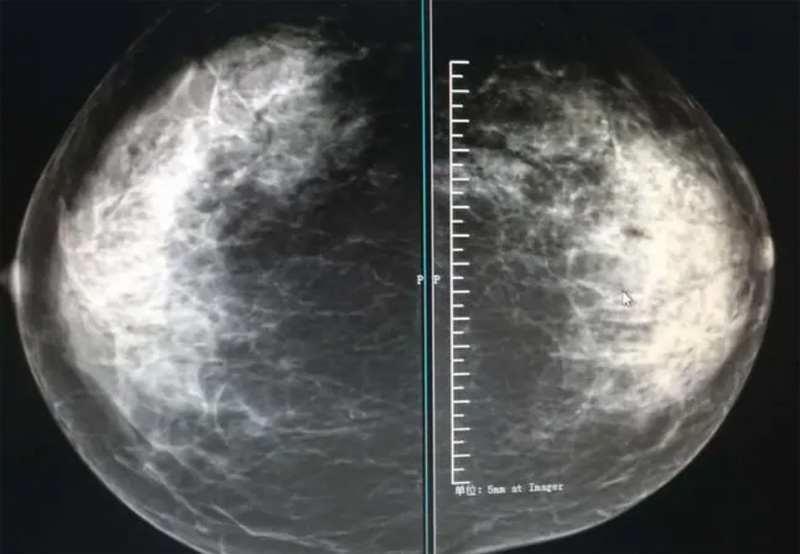

攝影診斷規(guī)范乳腺DR有頭尾位及內(nèi)外側(cè)斜位診斷概念和診斷術(shù)語

乳腺DR的檢查中為了讓乳腺相關(guān)疾病的篩查需要更高質(zhì)量的檢查圖像。檢查前期的準(zhǔn)備工作非常重要。醫(yī)生跟病患的有效溝通。要跟檢查者說明檢查過程,特別是體位跟擠壓乳房帶來的不適應(yīng)。放松心情,檢查過程中得到充分的合作。正確的擺正位置乳腺DR可以拍攝到更優(yōu)質(zhì)清洗高質(zhì)量的X線圖像。乳腺DR檢查需要再月經(jīng)后檢查,但是對病癥明顯的就不受這個限制。

乳腺DR攝影體位有頭尾位及內(nèi)外側(cè)斜位,

乳房在片子的中央,乳頭切線位,可見小部分胸大肌,內(nèi)側(cè)乳腺組織應(yīng)全部包括在片中,外側(cè)乳腺組織盡可能包括在片中。一張好的MLO位圖像顯示如下:乳房被推向前上,乳腺實質(zhì)充分展開,胸大肌可見,較松弛,下緣達(dá)到乳頭水平,乳頭在切線位,部分腹壁包括在片中,但與下部乳腺分開,絕大部分乳腺實質(zhì)顯示在片中。乳腺組織外緣可見乳頭的輪廓;乳腺后方的脂肪組織被很好地顯示出來,乳房無皺褶。對于CC位及MLO位顯示不良或未包全的乳腺實質(zhì),可以根據(jù)病灶位置的不同選擇以下體位:外內(nèi)側(cè)位(LM)、內(nèi)外側(cè)位(ML)、內(nèi)側(cè)頭尾軸位(MCC)、外側(cè)頭尾軸位(LCC),尾葉位(CLEO)及乳溝位。在臨床實踐中,對于常規(guī)體位上發(fā)現(xiàn)的異常改變,可以進(jìn)一步采取一些特殊的攝影技術(shù),包括局部加壓攝影、放大攝影或局部加壓放大攝影技術(shù)。

3、乳腺實質(zhì)背景的確定:觀察乳腺實質(zhì)與脂肪的構(gòu)成比例,了解乳腺實質(zhì)類型,以判斷對某些乳腺攝影征象敏感性的影響,有利于確定乳腺攝影對疾病的診斷價值。

必須指出的是,美國放射學(xué)會提出的乳腺影像報告和數(shù)據(jù)系統(tǒng)(Breast Imaging Reporting and Data System, BI-RADS)將乳腺分為4型:脂肪型(乳腺內(nèi)幾乎全部為脂肪組織,腺體組織占25%以下)、少量腺體型(乳腺內(nèi)散在腺體組織,大約占25%~50%)、多量腺體型(乳腺呈不均勻致密表現(xiàn),腺體組織大約占51%~75%)、致密型(乳腺組織非常致密,腺體組織占75%以上)。這種分型的主要意義在于說明X線對不同乳腺類型中病變檢出的敏感性不同,對發(fā)生在脂肪型乳腺中病變的檢出率很高,而對發(fā)生在致密型乳腺中病變的檢出率則有所降低,臨床醫(yī)師了解這一點(diǎn)很重要。